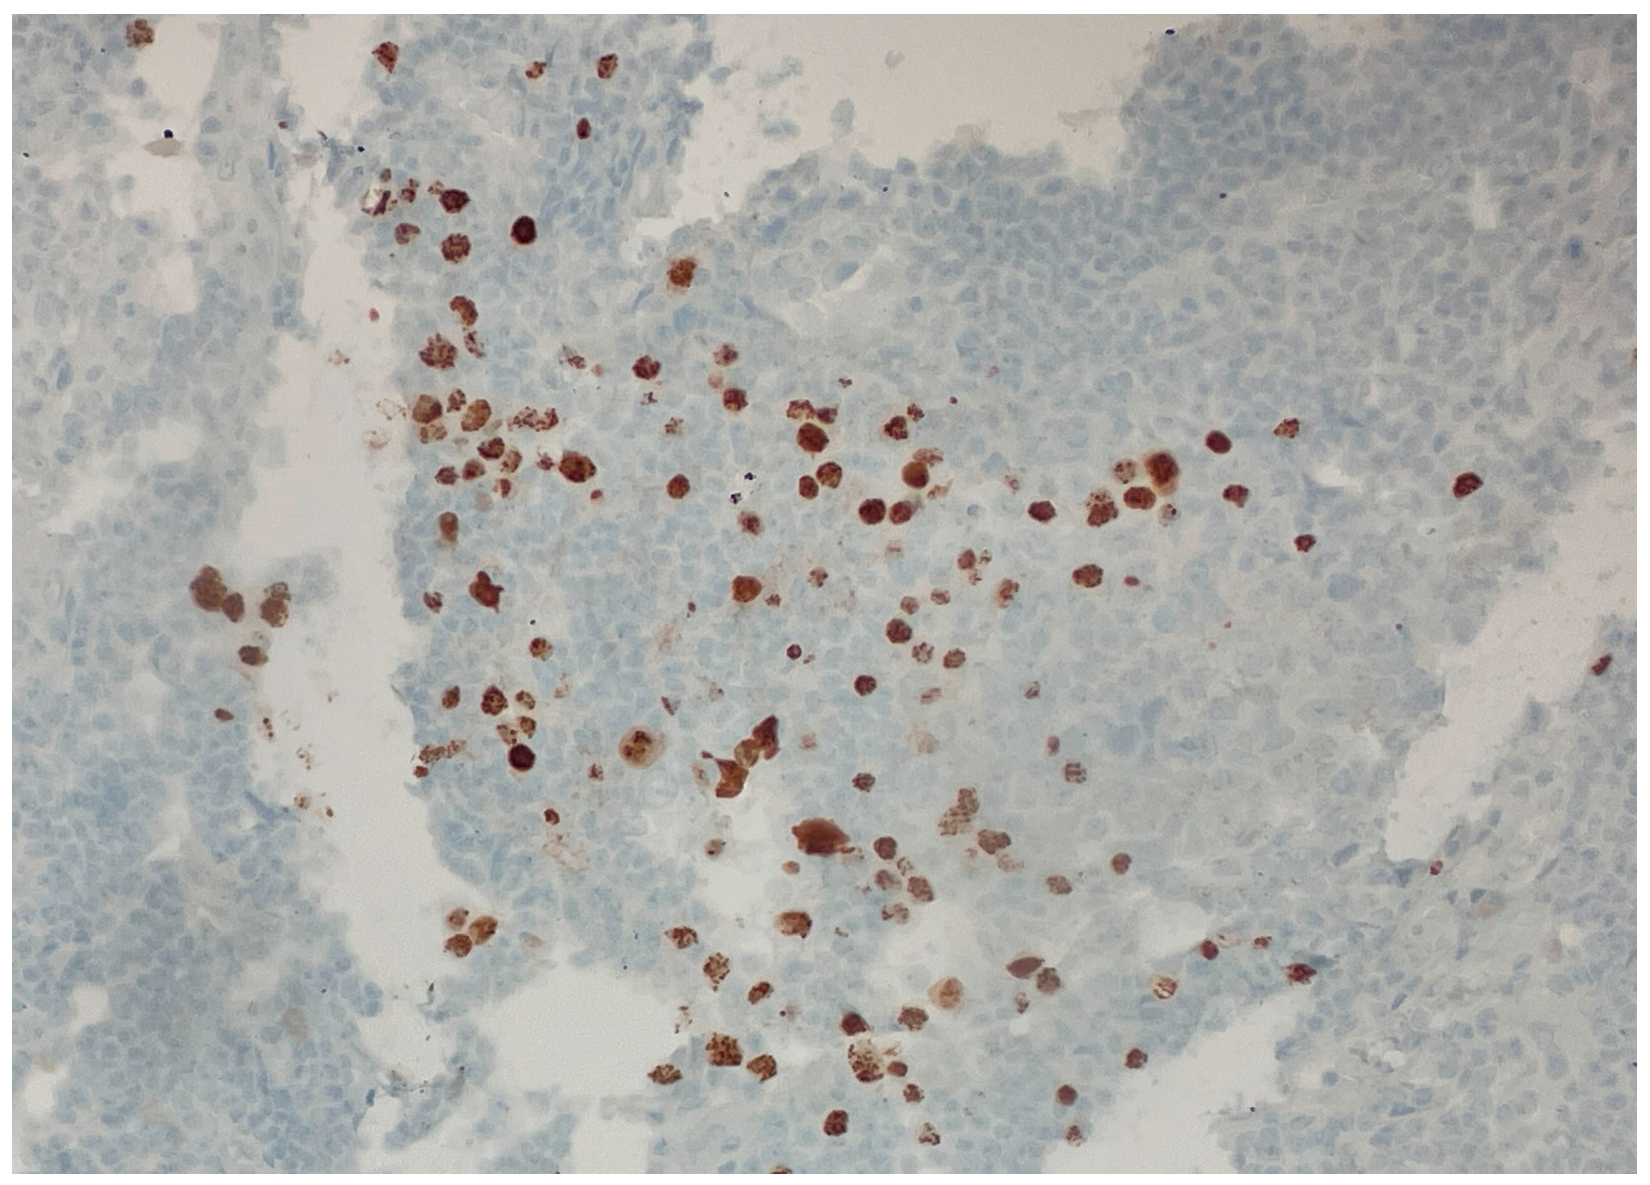

Over the following weeks, the patient developed ascites and worsening constitutional symptoms. An excisional biopsy of a lymph node was subsequently performed and demonstrated HHV-8-positive MCD, confirmed by immunohistochemical staining for LANA-1, showing scattered nuclear positivity in lymphoid cells (Figure 1). The histology also revealed characteristic “onion skinning” of mantle zone lymphocytes (Figure 2) and regressed germinal centers with increased interfollicular vascularity and hyalinization (Figure 3), findings consistent with HHV-8-associated MCD. Rituximab monotherapy was initiated, resulting in clinical improvement, resolution of the constitutional symptoms, and stabilization of ascites.

Figure 1. Immunohistochemical staining demonstrating HHV-8 (LANA-1) positivity. (40×). Scattered brown nuclear staining in lymphoid cells indicates the presence of latent HHV-8 infection, consistent with HHV-8-associated multicentric Castleman disease. This staining pattern confirms the presence of latent nuclear antigen-1 (LANA-1), a specific marker for HHV-8-infected cells.

The distinction between a core needle and excisional biopsy is critical because delays in performing excisional biopsies frequently prolong the diagnostic timeline, consequently delaying the initiation of essential treatment. In accordance with published consensus criteria, the excisional biopsy for our patient not only confirmed the diagnosis, but also revealed classic MCD histopathologic features, including the characteristic “onion skinning” mantle zones and the presence of LANA-1-positive plasmablasts [1].